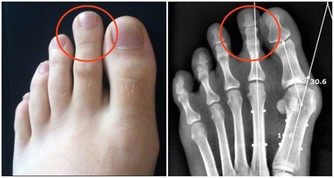

早衰,健忘失眠,食欲不振,骨骼與關節疼痛,腰膝酸軟,不耐疲勞,乏力,視力減退,聽力衰減。

脫髮白髮、頭髮脫落或須發早白,牙齒鬆動易落等。